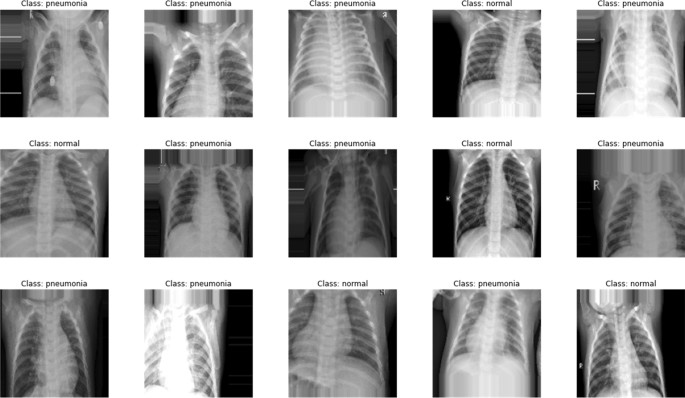

This section presents the findings of the CareAssist-GPT model’s classification when used to identify pneumonia from chest X-ray images. The test images were provided and labelled as either having pneumonia or being normal. Some of the classified images are shown in the Fig. 10 below. The figure shows each image with its class to indicate the diagnostic result given by the model.

The classification results have shown the effectiveness of the model at distinguishing between cases of pneumonia and non-pneumonia. As depicted in Fig. 10, the model is able to successfully detect regions of infection suggesting pneumonia as well as normal lung tissue. These findings lend credence to the model for utilization in reliable diagnostic settings in clinical practice.